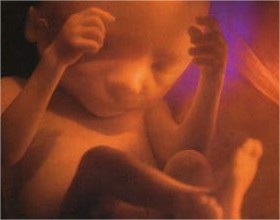

21 Semanas de Gestação

Sua 21a semana começa

Outra coisa que é familiar ao bebê depois do nascimento é o som das batidas do coração da mamãe, um som dos céus para ele. Agora com 21 semanas, o bebê já pode pesar cerca de 360 gramas e medir aproximadamente 26 cm! Como cresceu, não?

Gravidez de 21 semanas são quantos meses? Estamos na última semana do 5º mês de gestação e o principal desenvolvimento nesta semana é o dos ossos1. Vale destacar que a produção dos glóbulos vermelhos no sangue também é iniciada e os vasos sanguíneos ficam totalmente nítidos sob a pele, que ainda é rosada e transparente.

Seu pequeno corpo não possui muita gordura, algo que se modificará nas próximas semanas quando será necessário um certo acúmulo adiposo para ser utilizado como fonte de energia e suporte de temperatura após o nascimento.

A aparência já é a do bebezinho que irá nascer, só que ainda muito pequeno. Seu tamanho é parecido com o de uma banana e a partir desta fase o peso vai aumentar bem rápido até o dia do nascimento.

Qual o peso do bebê com 21 Semanas de Gestação?

O peso do bebê varia de um para o outro, mas normalmente se encontra entre 280 a 370 gramas, medindo em média 23 centímetros.